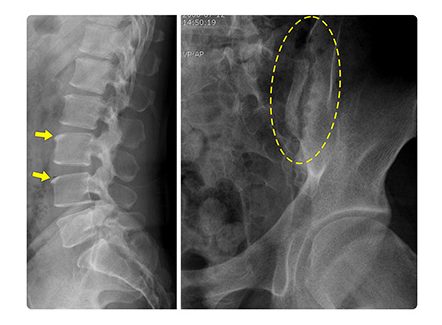

검사 방법 🔬

- 영상 검사: X-ray, MRI (조기 진단에 더 민감)

MRI는 증상이 나타난 초기부터 병변 확인 가능해서 요즘 가장 많이 활용됩니다.